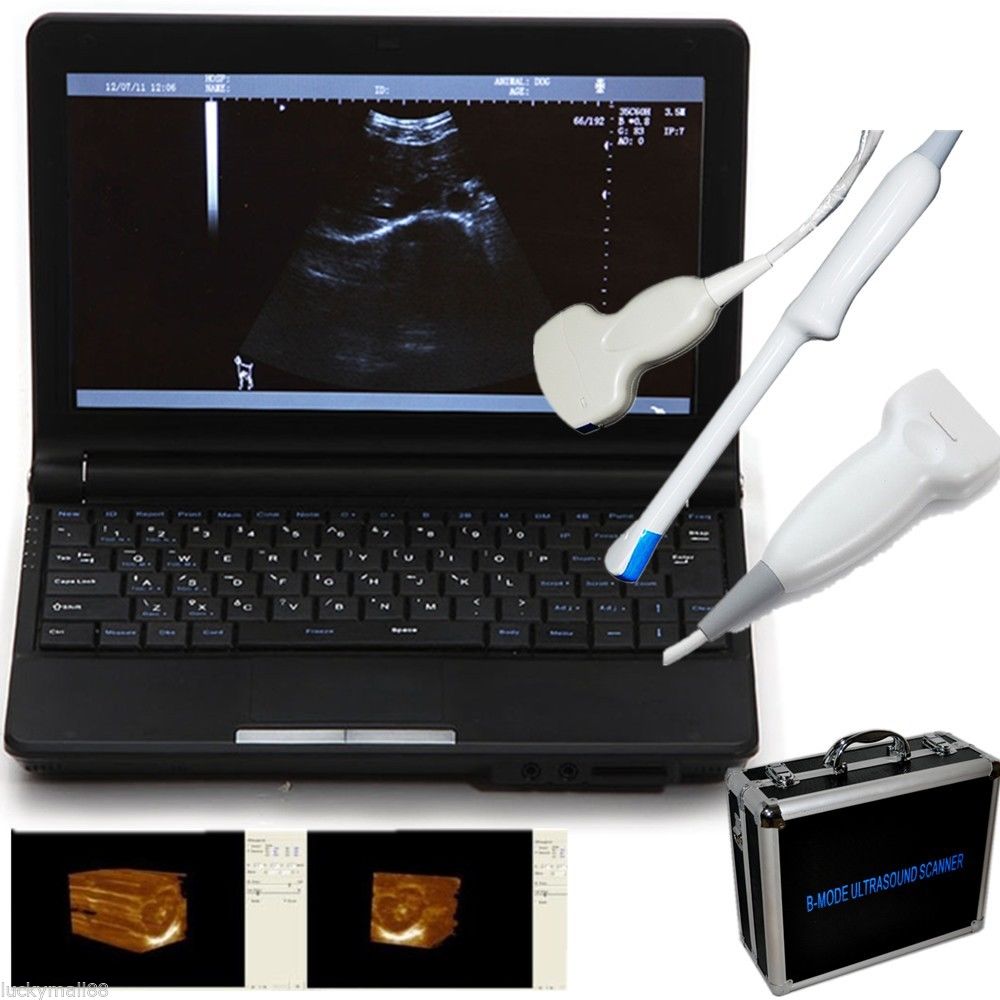

DIAGNOSTIC ULTRASOUND MACHINES FOR SALE

Laptop Ultrasound Machine, Notebook Digital Ultrasound scanner, 3.5 Convex probe

Sale price$ 1,648.00

Regular price$ 1,758.00